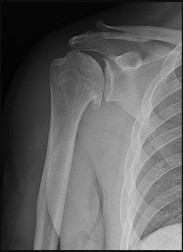

Figures 32a through 32c are the radiograph and CT scans of a 75-year-old smoker with hypertension who sustained a ground-level fall without loss of consciousness with impact to her

The radiographs and CT scans indicate a 4-part left proximal humerus fracture with tuberosity comminution. Based upon her preinjury level of activity and current imaging studies, nonsurgical management is not the correct option to restore her ability to perform activities of daily living, including hygiene care. There has been enthusiasm among surgeons regarding the use of the reverse shoulder prosthesis as the primary mode of surgical treatment of certain 3- and 4-part proximal humerus fractures. The main attribute of this implant is its ability to achieve functional shoulder forward flexion and abduction regardless of tuberosity healing, position, and degree of comminution. Nevertheless, repair and union of the greater tuberosity fragment during rTSA demonstrate improved external rotation, clinical outcomes, and patient satisfaction than outcomes achieved after tuberosity resection, nonunion, or resorption. Based upon this patient’s age and imaging findings, an rTSA would provide pain relief and improved function with complication rates similar to those associated with hemiarthroplasty. Open reduction with internal fixation would not be a viable option because of the high probability for a dysvascular head, increased risk for nonunion, and potential for revision surgery, including arthroplasty. Hemiarthroplasty for 4-part proximal humerus fractures remains a viable option for patients younger than 70 years of age with minimal tuberosity comminution and an intact rotator cuff who can comply with a postsurgical rehabilitation program. Most studies indicate significant pain relief with this modality with significant variation in functional outcomes. In this clinical scenario, the patient’s injury may not be best served with hemiarthroplasty because of uncertainty regarding functional outcome.